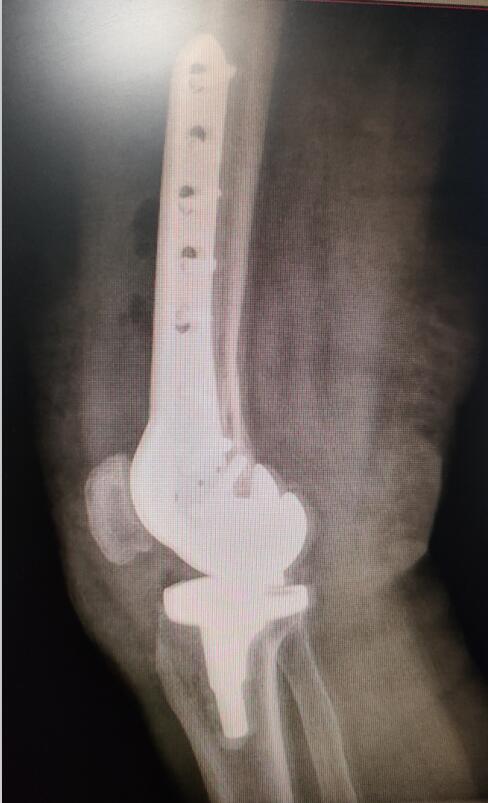

手術(shù)后照片

12月7日,在醫(yī)護(hù)團(tuán)隊(duì)的默契合作下,歷時(shí)1個(gè)多小時(shí),吳阿姨的手術(shù)順利完成。經(jīng)過(guò)兩周的后續(xù)治療,吳阿姨已經(jīng)可以站起來(lái),借助拐杖行走。“醫(yī)生們這次又讓我站起來(lái)了。”吳阿姨開(kāi)心地說(shuō)。

“關(guān)節(jié)假體需要進(jìn)行‘翻修’固定,要保證骨折部位修復(fù)后假體的穩(wěn)定性,還要考慮患者年齡大,曾接受過(guò)多次手術(shù),患有多種基礎(chǔ)疾病,手術(shù)技術(shù)難度高,對(duì)醫(yī)生和患者都是一次挑戰(zhàn)?!弊鳛槭中g(shù)團(tuán)隊(duì)成員和吳阿姨主管醫(yī)生的王旌晶覺(jué)得一定要對(duì)得起患者及家屬這份沉甸甸的信任。

“隨著骨科關(guān)節(jié)置換技術(shù)的飛速發(fā)展,老年髖關(guān)節(jié)假體和膝關(guān)節(jié)假體周?chē)钦鄣幕颊邤?shù)量不斷增加,這類(lèi)患者往往合并有多種基礎(chǔ)疾病,手術(shù)難度更高,各種要求也更高。” 王旌晶說(shuō),醫(yī)院骨傷三科在李彬主任的帶領(lǐng)下,經(jīng)過(guò)多年對(duì)老年人骨折處理的經(jīng)驗(yàn)總結(jié),對(duì)于這類(lèi)患者還是有相當(dāng)豐富的手術(shù)經(jīng)驗(yàn)和技巧,“假體周?chē)钦凼中g(shù)”開(kāi)展后大大降低了老年人此類(lèi)骨折后并發(fā)癥的發(fā)生,明顯改善患者的生活質(zhì)量,“解放了”患者家屬。